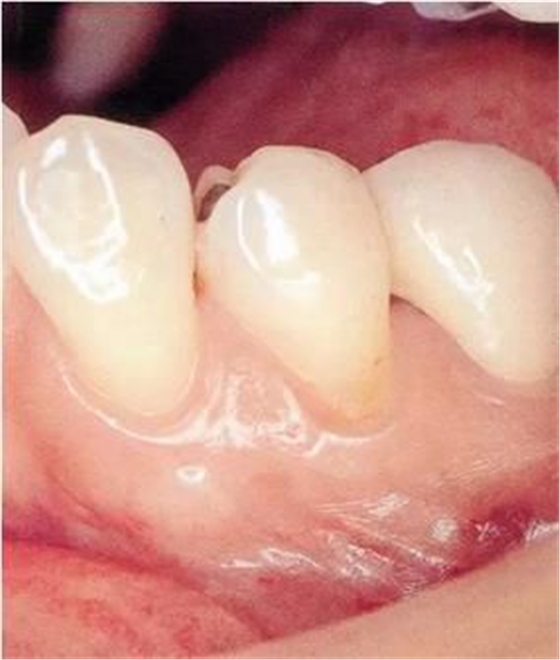

▲圖1

牙位異常例①。由于牙列擁擠造成牙根接近。